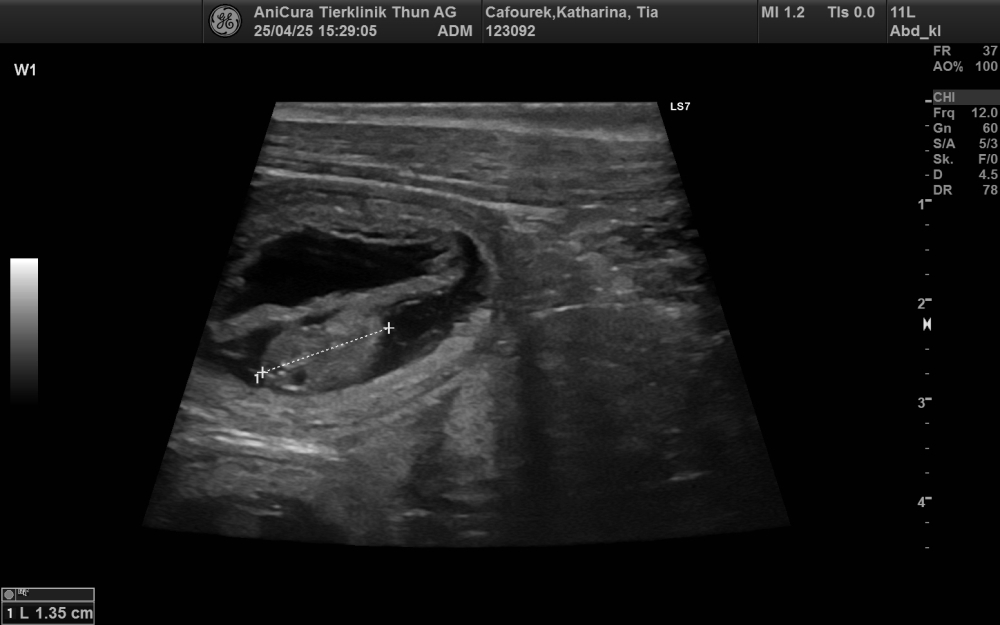

27.10.2025 Current picture of our Roxy »more... 25.07.2025 Stuck and portrait pics of the Swiss dwarfs »more... 29.05.2025 Eight Swiss dwarfs have landed »more... 17.05.2025 Puppy meeting at Marie and Dirk »more... 25.04.2025 Shumbazino Hatia Feelena Tia und Hunterholm Dacapo Moyoni Mo will become parents »more... 05.02.2025 Litter planning in the kennel Kutoka Uswisi »more... 24.12.2024 Merry Christmas 2024 »more... 16.11.2024 Tilda and Fatouk are family »more... All news... |